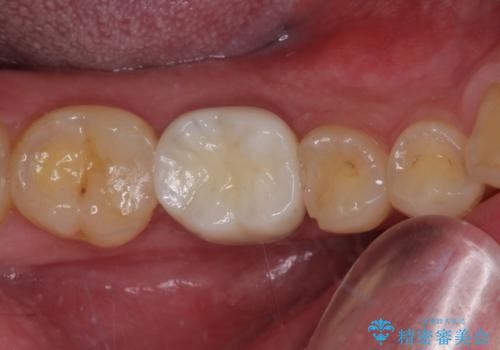

- 歯が欠損したままの奥歯のクラウンが欠けているとのことで来院された患者様です。

右上の一番奥の歯が欠損しており、その手前の歯2つを土台に連結されたクラウンが装着されていました。

不安定な咬み合わせとなっており、クラウンの表面が剥離していたため、インプラントによる欠損補綴治療を行い、手前2つの歯も一緒に補綴治療を行うこととしました。